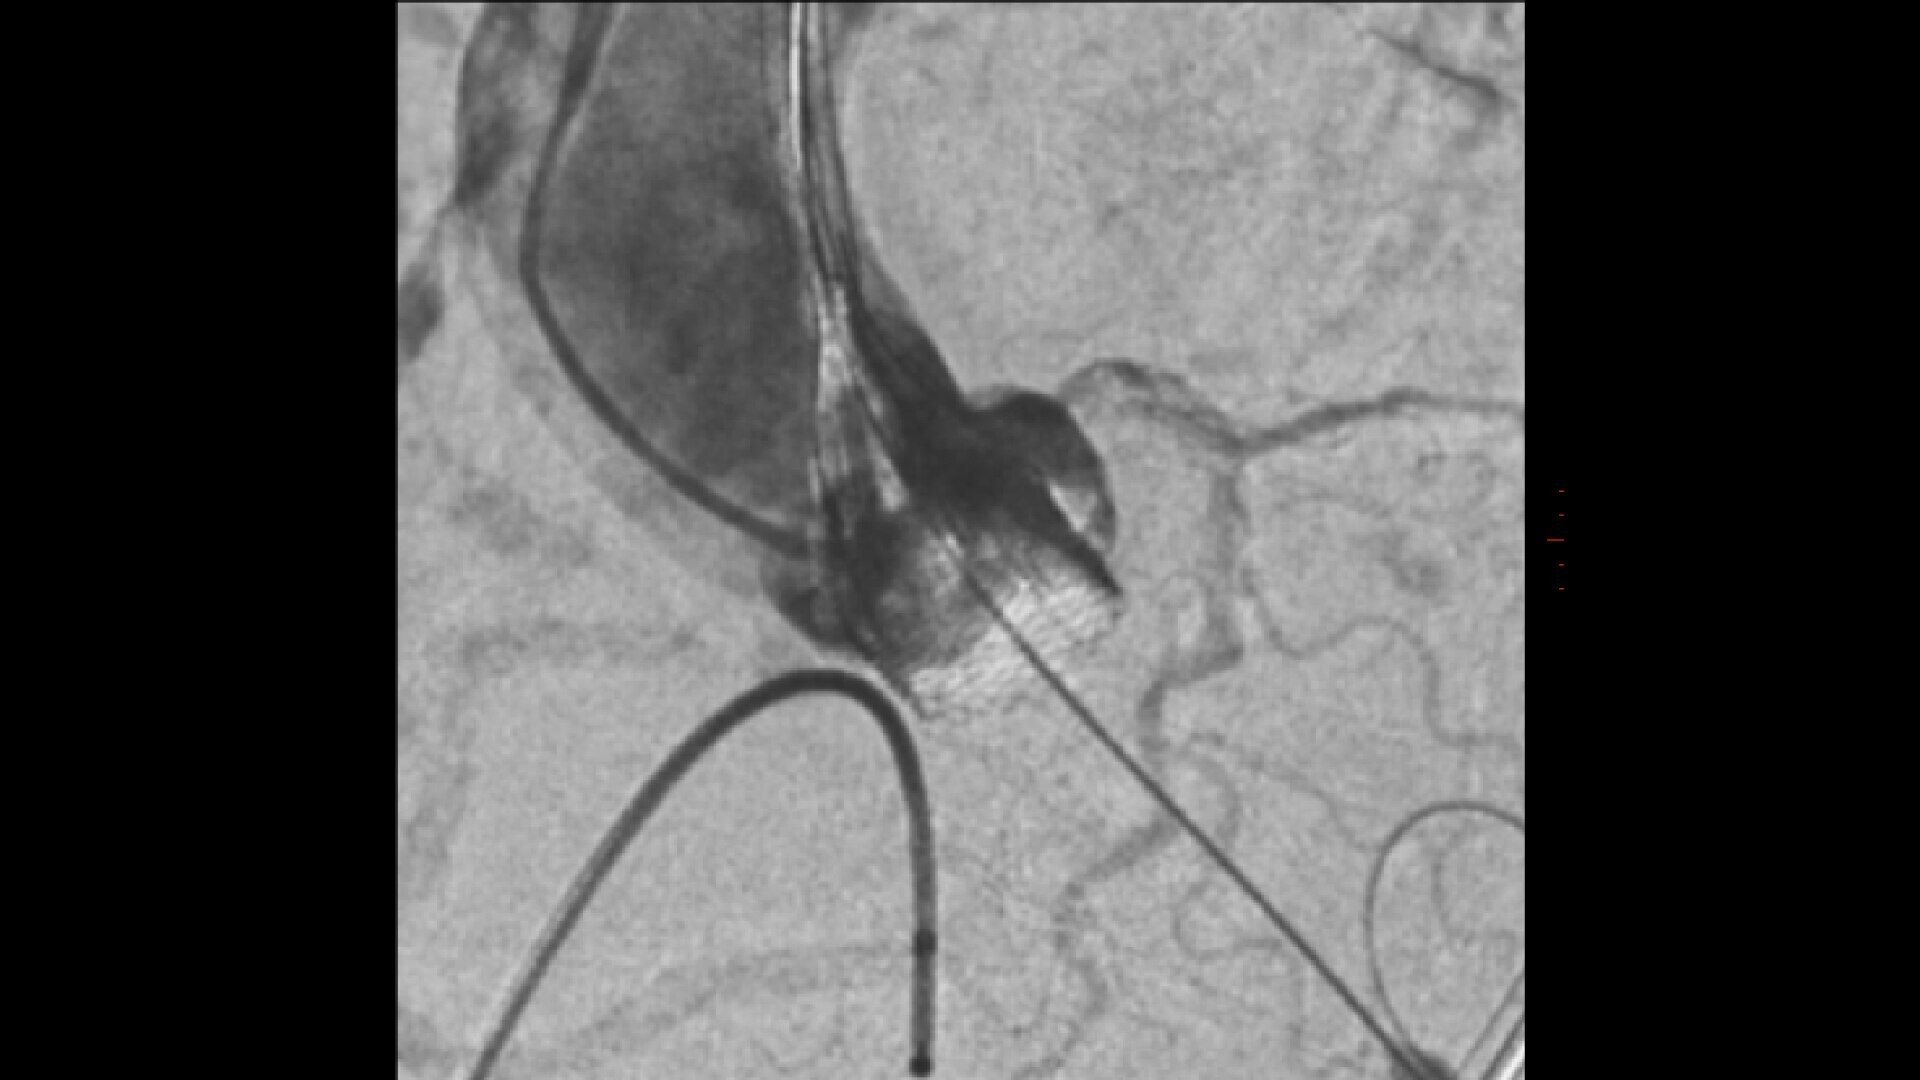

ASSESS

Assess potential regurgitation with exceptional contrast visualization.